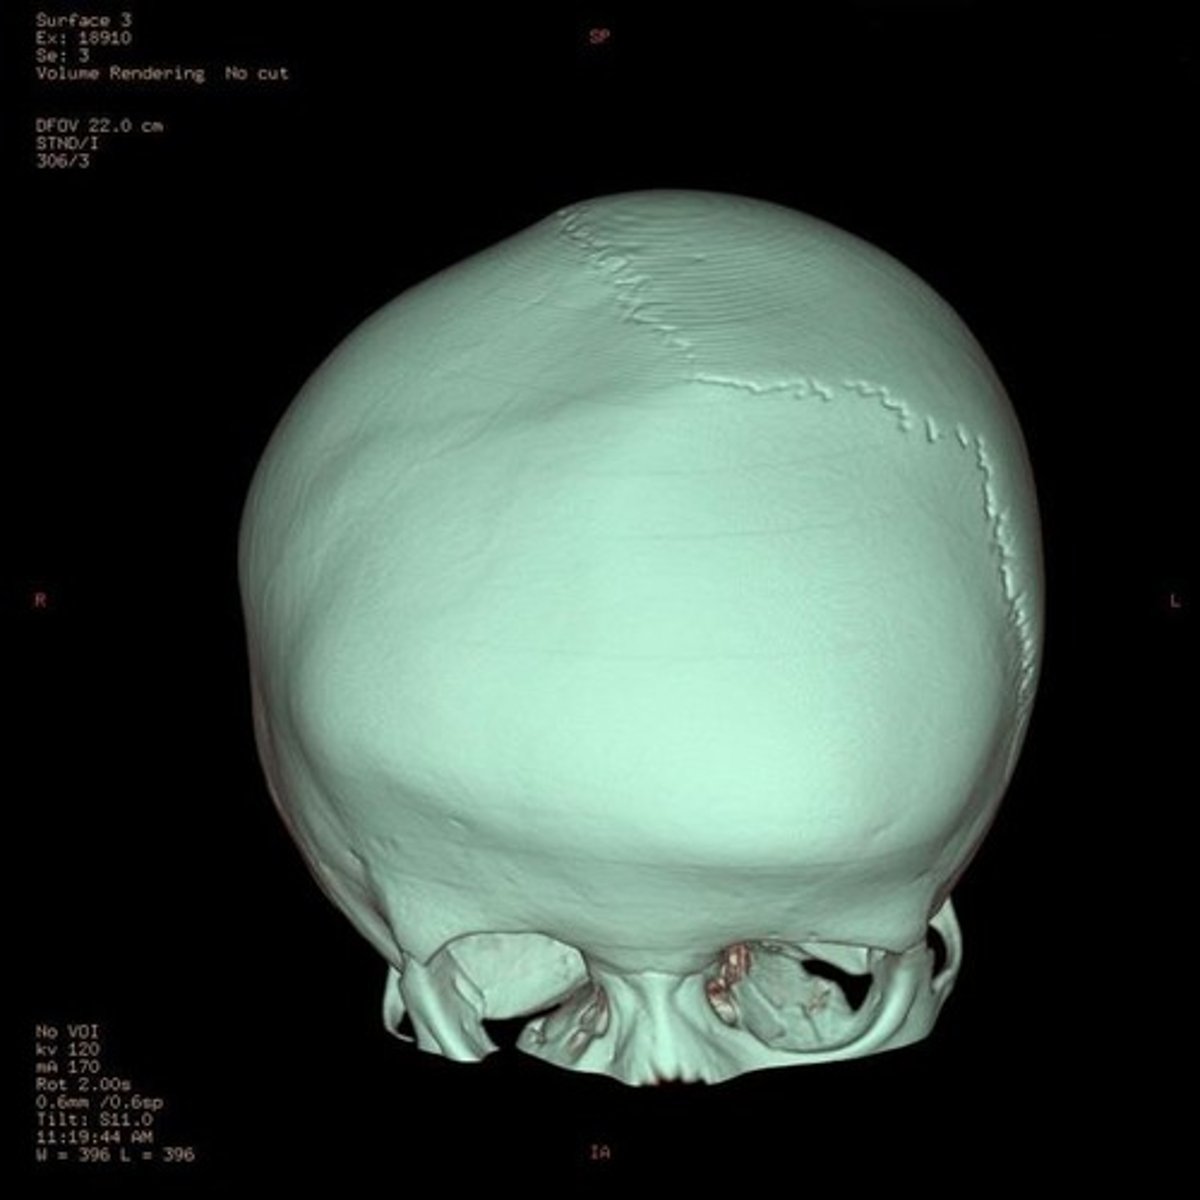

lambdoid suture

between parietal bones and occipital bone

lambdoid craniosynostosis

closing of one side of the lambdoid suture resulting in posterior bulging at the contralateral side